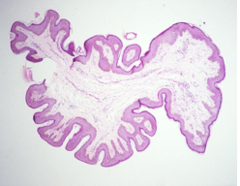

thick skin

Front

what type of skin is this?

Back